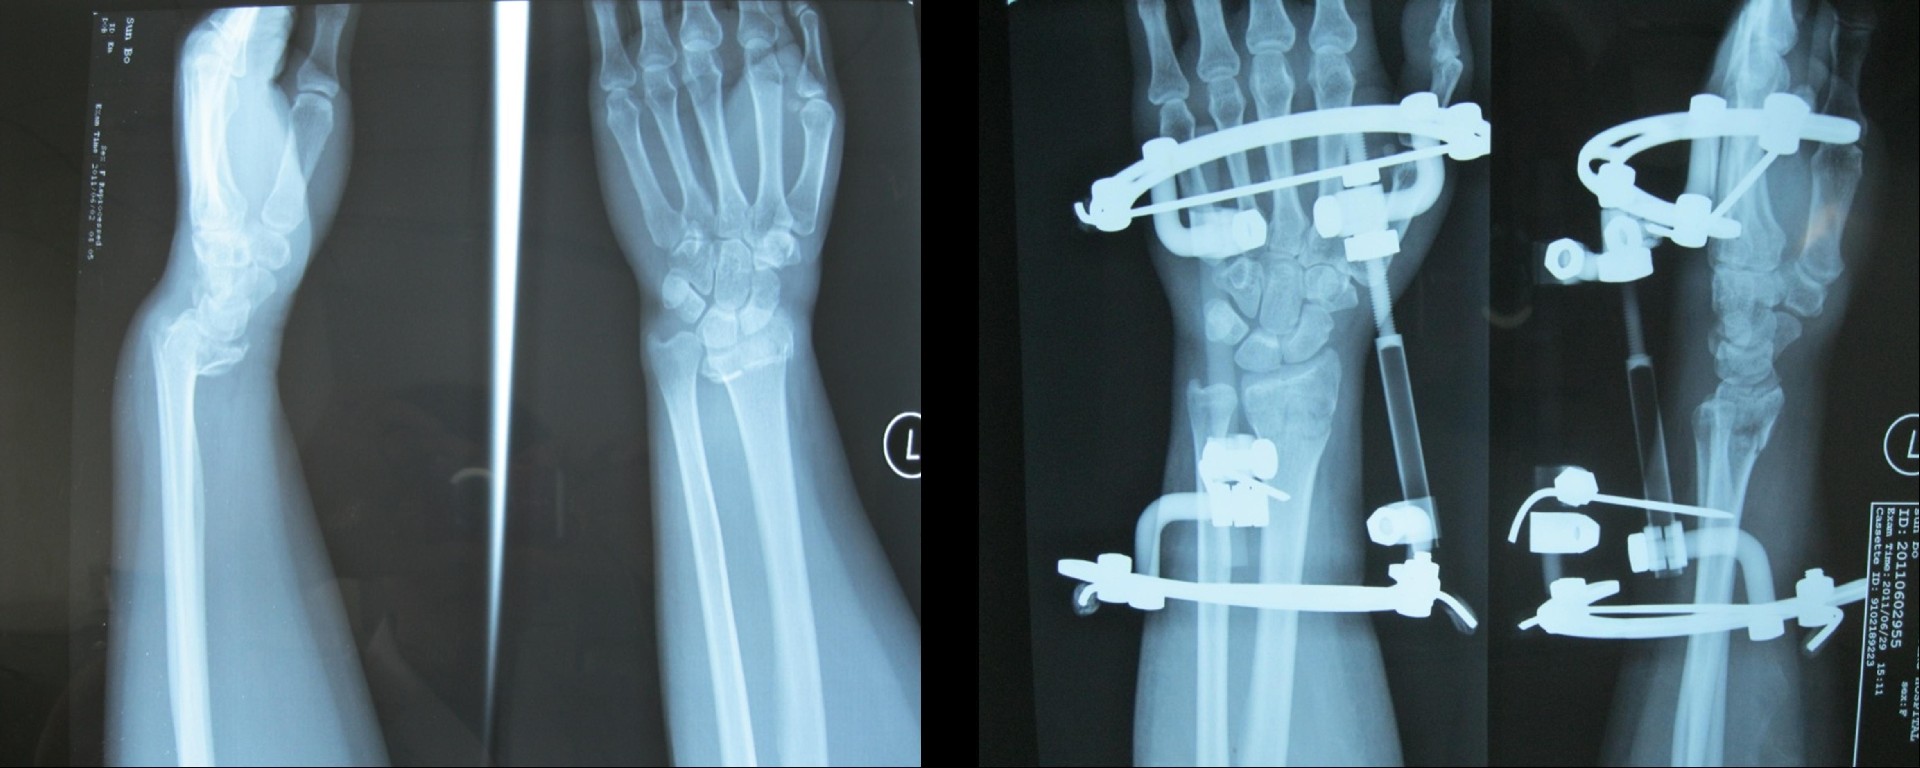

研獨家產品組合式三維骨科牽引固定架,秉承Ilizarov技術理念。采用環(huán)形結構為主,具有專利保護,組裝簡便,穿針便捷,適合各種骨折、畸形矯正、肢體延長等手術。

馬蹄半環(huán)小腿架構型

半環(huán)構型,適合脛骨骨折加壓固定及骨延長。

改良馬蹄半環(huán)型股骨延長外固定架